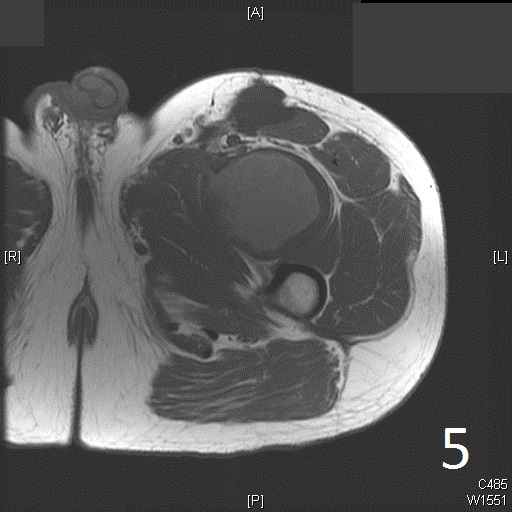

• 60% of fibrosarcomas are intramuscular (Fig. 2, 3, 5, 6, 7, 8)

Fig. 5-9: Axial and sagittal (Fig. 6) MRI shows a fibrosarcoma in the proximal quadriceps muscle that is isointense to muscle on T1W images, and a heterogeneous on T2W FS (Fig. 7, 8). The patient was treated with preoperative chemotherapy and the mass underwent extensive necrosis. The mass does not show any enhancement with contrast due to the extensive necrosis. There is only peripheral enhancement with contrast on T1W FS (Fig. 9).